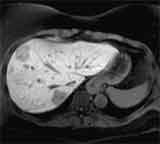

| T2-gewichtet | T1-gewichtet 30 Sekunden nach Kontrastmittelgabe |